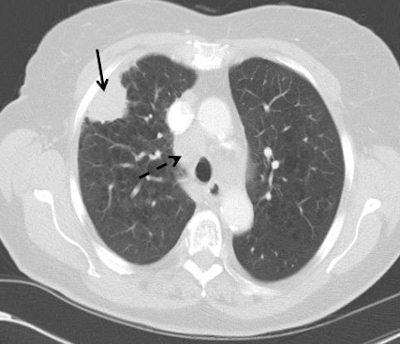

CT detects many benign nodules and masses (about 25 for every cancer detected), they continued. In the National Lung Screening Trial (NLST), 59/26,722 (0.2%) of participants underwent a CT-guided lung biopsy for a benign lesion and seven (0.03%) had a major complication. Clinical management pathways were not prespecified in the NLST, and where data were available, 2.2% of participants underwent PET, thus receiving a much higher radiation dose. The Dutch-Belgian NELSON trial and the UKLS pilot trial both employ low-dose CT follow-up by using volume measurements rather than diameter to detect growth, and this reduces the number of false-positive screens and defines more accurately the need for invasive procedures.